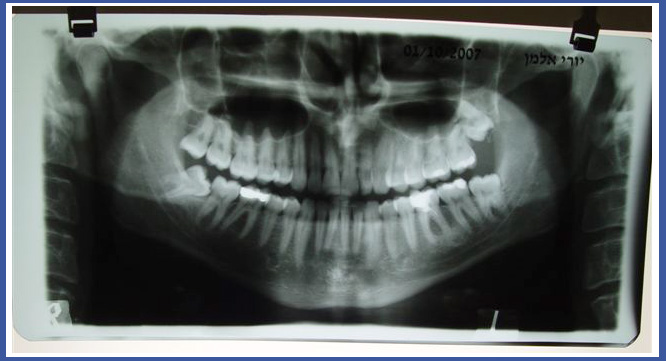

5. Панорамный снимок:

Это снимок, который выполняется в рентгеновском кабинете и включает обе челюсти сразу. Панорамный снимок показывает врачу анатомию челюстей и зубов в двухмерном измерении. На снимке видна и анатомия части черепа, начиная с глазного дна; носовые пазухи и челюсти, челюстные суставы и т. д.

Снимок обычно выполняется перед удалением зубов мудрости – для проверки близости зуба к нервному каналу, а также перед имплантацией зубов в качестве первичной диагностической меры, предоставляющей врачу общую информацию в отношении носовых пазух, высоты кости и расположения нерва. В тех случаях, когда существует какая-либо патология (опухоль, рана, распространившееся воспаление), снимок – это прекрасное первичное диагностическое средство.